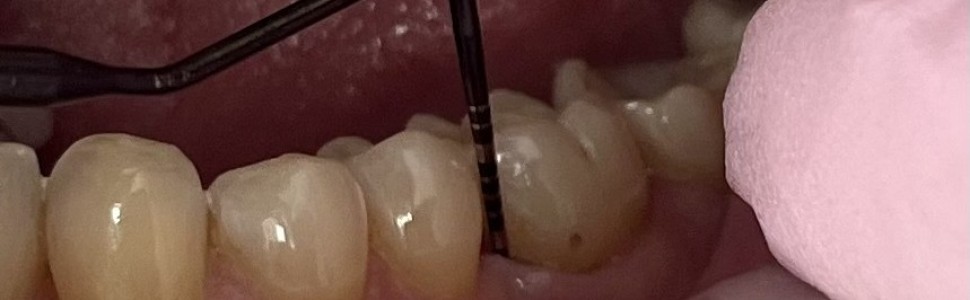

Zapalenie przyzębia to wieloczynnikowa choroba, która może wystąpić również u osób w młodym wieku. Zazwyczaj charakteryzuje się wtedy wysokim tempem progresji i szybką destrukcją tkanek przyzębia, nieadekwatną do wieku i ilości złogów nazębnych. Dodatkową komplikacją, pogarszającą rokowanie, są stany zapalne miazgi i obecność zmian okołowierzchołkowych. Jednak odpowiednio wczesne postawienie trafnej diagnozy i podjęcie intensywnego leczenia, połączone z dobrą współpracą z pacjentem, daje optymistyczne rokowania. Poniższy opis przypadku prezentuje leczenie 28-letniej pacjentki z zapaleniem przyzębia w stadium III i stopniem C, które doprowadziło do remisji choroby i zachowania wszystkich zębów własnych, włącznie z zębem 36 z zespołem endo-perio, pierwotnie zakwalifikowanym do usunięcia.

Periodontitis is a multifactorial disease that can also occur in people at a young age. It is usually characterized by a high rate of progression and rapid destruction of periodontal tissues, inadequate to the age and number of dental deposits. An additional complication that worsens the prognosis is inflammation of the pulp and the presence of periapical lesions. However, early diagnosis and intensive treatment, combined with good cooperation with the patient, gives an optimistic prognosis. The following case report presents the treatment of a 28-year-old patient with stage III and stage C periodontitis, which led to remission of the disease and preservation of all her own teeth, including tooth 36 with endo-perio syndrome, originally qualified for extraction.